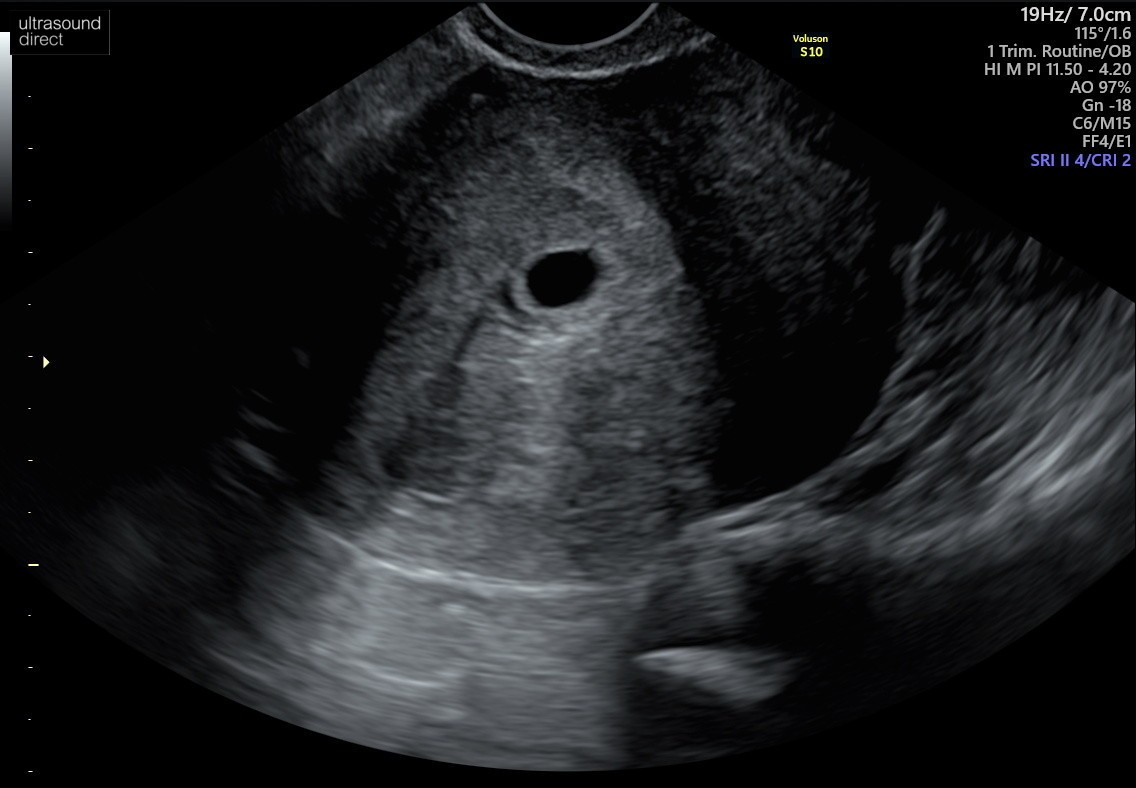

Witam , jestem w Uk - stad moje mega obawy chyba. Ostatnia miese miałam 7/08. Test pozytywny 4/09 w dzień spodziewanej miesiączki. Według obliczeń poszliśmy na usg w 7+6 tyg (25.09). Babeczka robiąc usg wykryła puste jajo płodowe z nawiązką krwi obok jaja. Powiedziała ze może to być puste, małe jajo płodowe albo 5 tydz ciąży dopiero, z tym ze nie jest widoczne ciałko żółte. Dwa dni po badaniu plamienia różowe , potem brązowe, bol brzucha pojechaliśmy do szpitala - dalej pusto ale mówią , plamienia to normalka, bol brzucha to normalka No i czekać za dwa tyg scan. Według moich obliczeń mega niemożliwością jest żebyśmy byli w piątym tyg dopiero bo sex uprawialiśmy 19/08 (20/08 wypadała ovulacja) prosze bez ocianiania ale potem nie mieliśmy sexu do 3/9 dzień nastepny robiłam test który wyszedł pozytywnie. Ja rozumiem ze może się wszystko poprzesuwać ale cykle mam co 28 dni, regularne. No i te plamienia teraz z bolącymi plecami i podbrzuszem. Zamartwiam się totalnie. Mial ktoś taka sytuacje ? Kiedy wszystko wydaje się kalendarzykowo a jednak te 2 wielkie tyg wszystko się przesunęło ??

A to z mojego skanu (25/09)

Mam możliwość pójścia prywatnie w piątek 30/09, na scan znowu ale nie wiem czy jestem w stanie usłyszeć po raz 3 puste jajo płodowe.